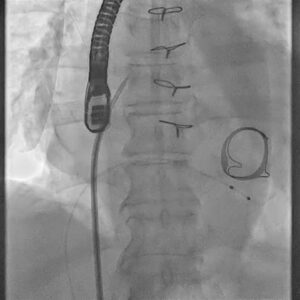

Figure 1. Baseline fluoroscopic procedural still showing prior surgical mitral prosthesis region and catheter setup.

This case involved an 81-year-old gentleman with a history of rheumatic heart disease who had previously undergone surgical mitral valve replacement and tricuspid valve repair on 23 July 2014. During that earlier operation, he received a 29 mm Perimount Edwards Lifesciences bioprosthetic mitral valve along with a TARP 29 St. Jude Medical annuloplasty ring.

He presented with symptomatic bradycardia and decompensated heart failure. Evaluation revealed degeneration of the mitral bioprosthesis with severe prosthetic stenosis and a mitral valve area of approximately 0.8 cm². Additional findings included marked biatrial enlargement, moderate tricuspid regurgitation, and pulmonary hypertension. During admission, he developed complete heart block with a ventricular rate of around 25 beats per minute, requiring urgent temporary pacing and intensive haemodynamic stabilisation.